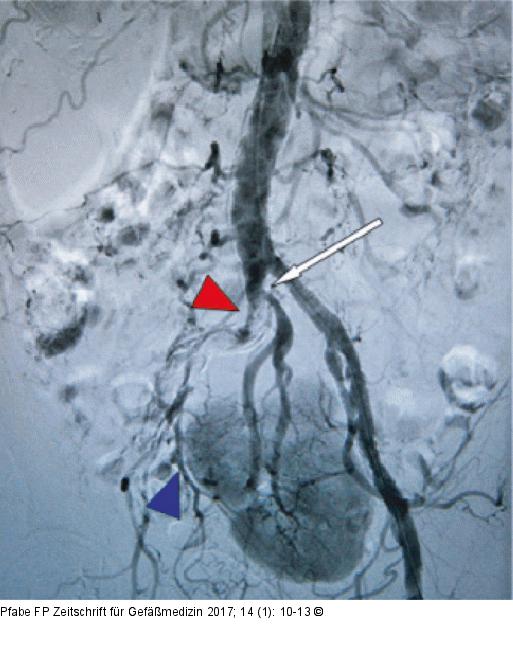

Abbildung 1: Beckenübersicht DSA-Beckenübersicht. Verschluss der A. iliaca communis rechts (roter Pfeil) und Demaskierung einer Nierenektopie mit verschlussnahem Abgang („upstream“) der Nierenarterie (weißer Pfeil), retrograde Perfusion der proximal verschlossenen A. iliaca interna (blauer Pfeil). Eine orthotope Niere kommt nicht zur Darstellung. |

Abbildung 1: Beckenübersicht

DSA-Beckenübersicht. Verschluss der A. iliaca communis rechts (roter Pfeil) und Demaskierung einer Nierenektopie mit verschlussnahem Abgang („upstream“) der Nierenarterie (weißer Pfeil), retrograde Perfusion der proximal verschlossenen A. iliaca interna (blauer Pfeil). Eine orthotope Niere kommt nicht zur Darstellung. |